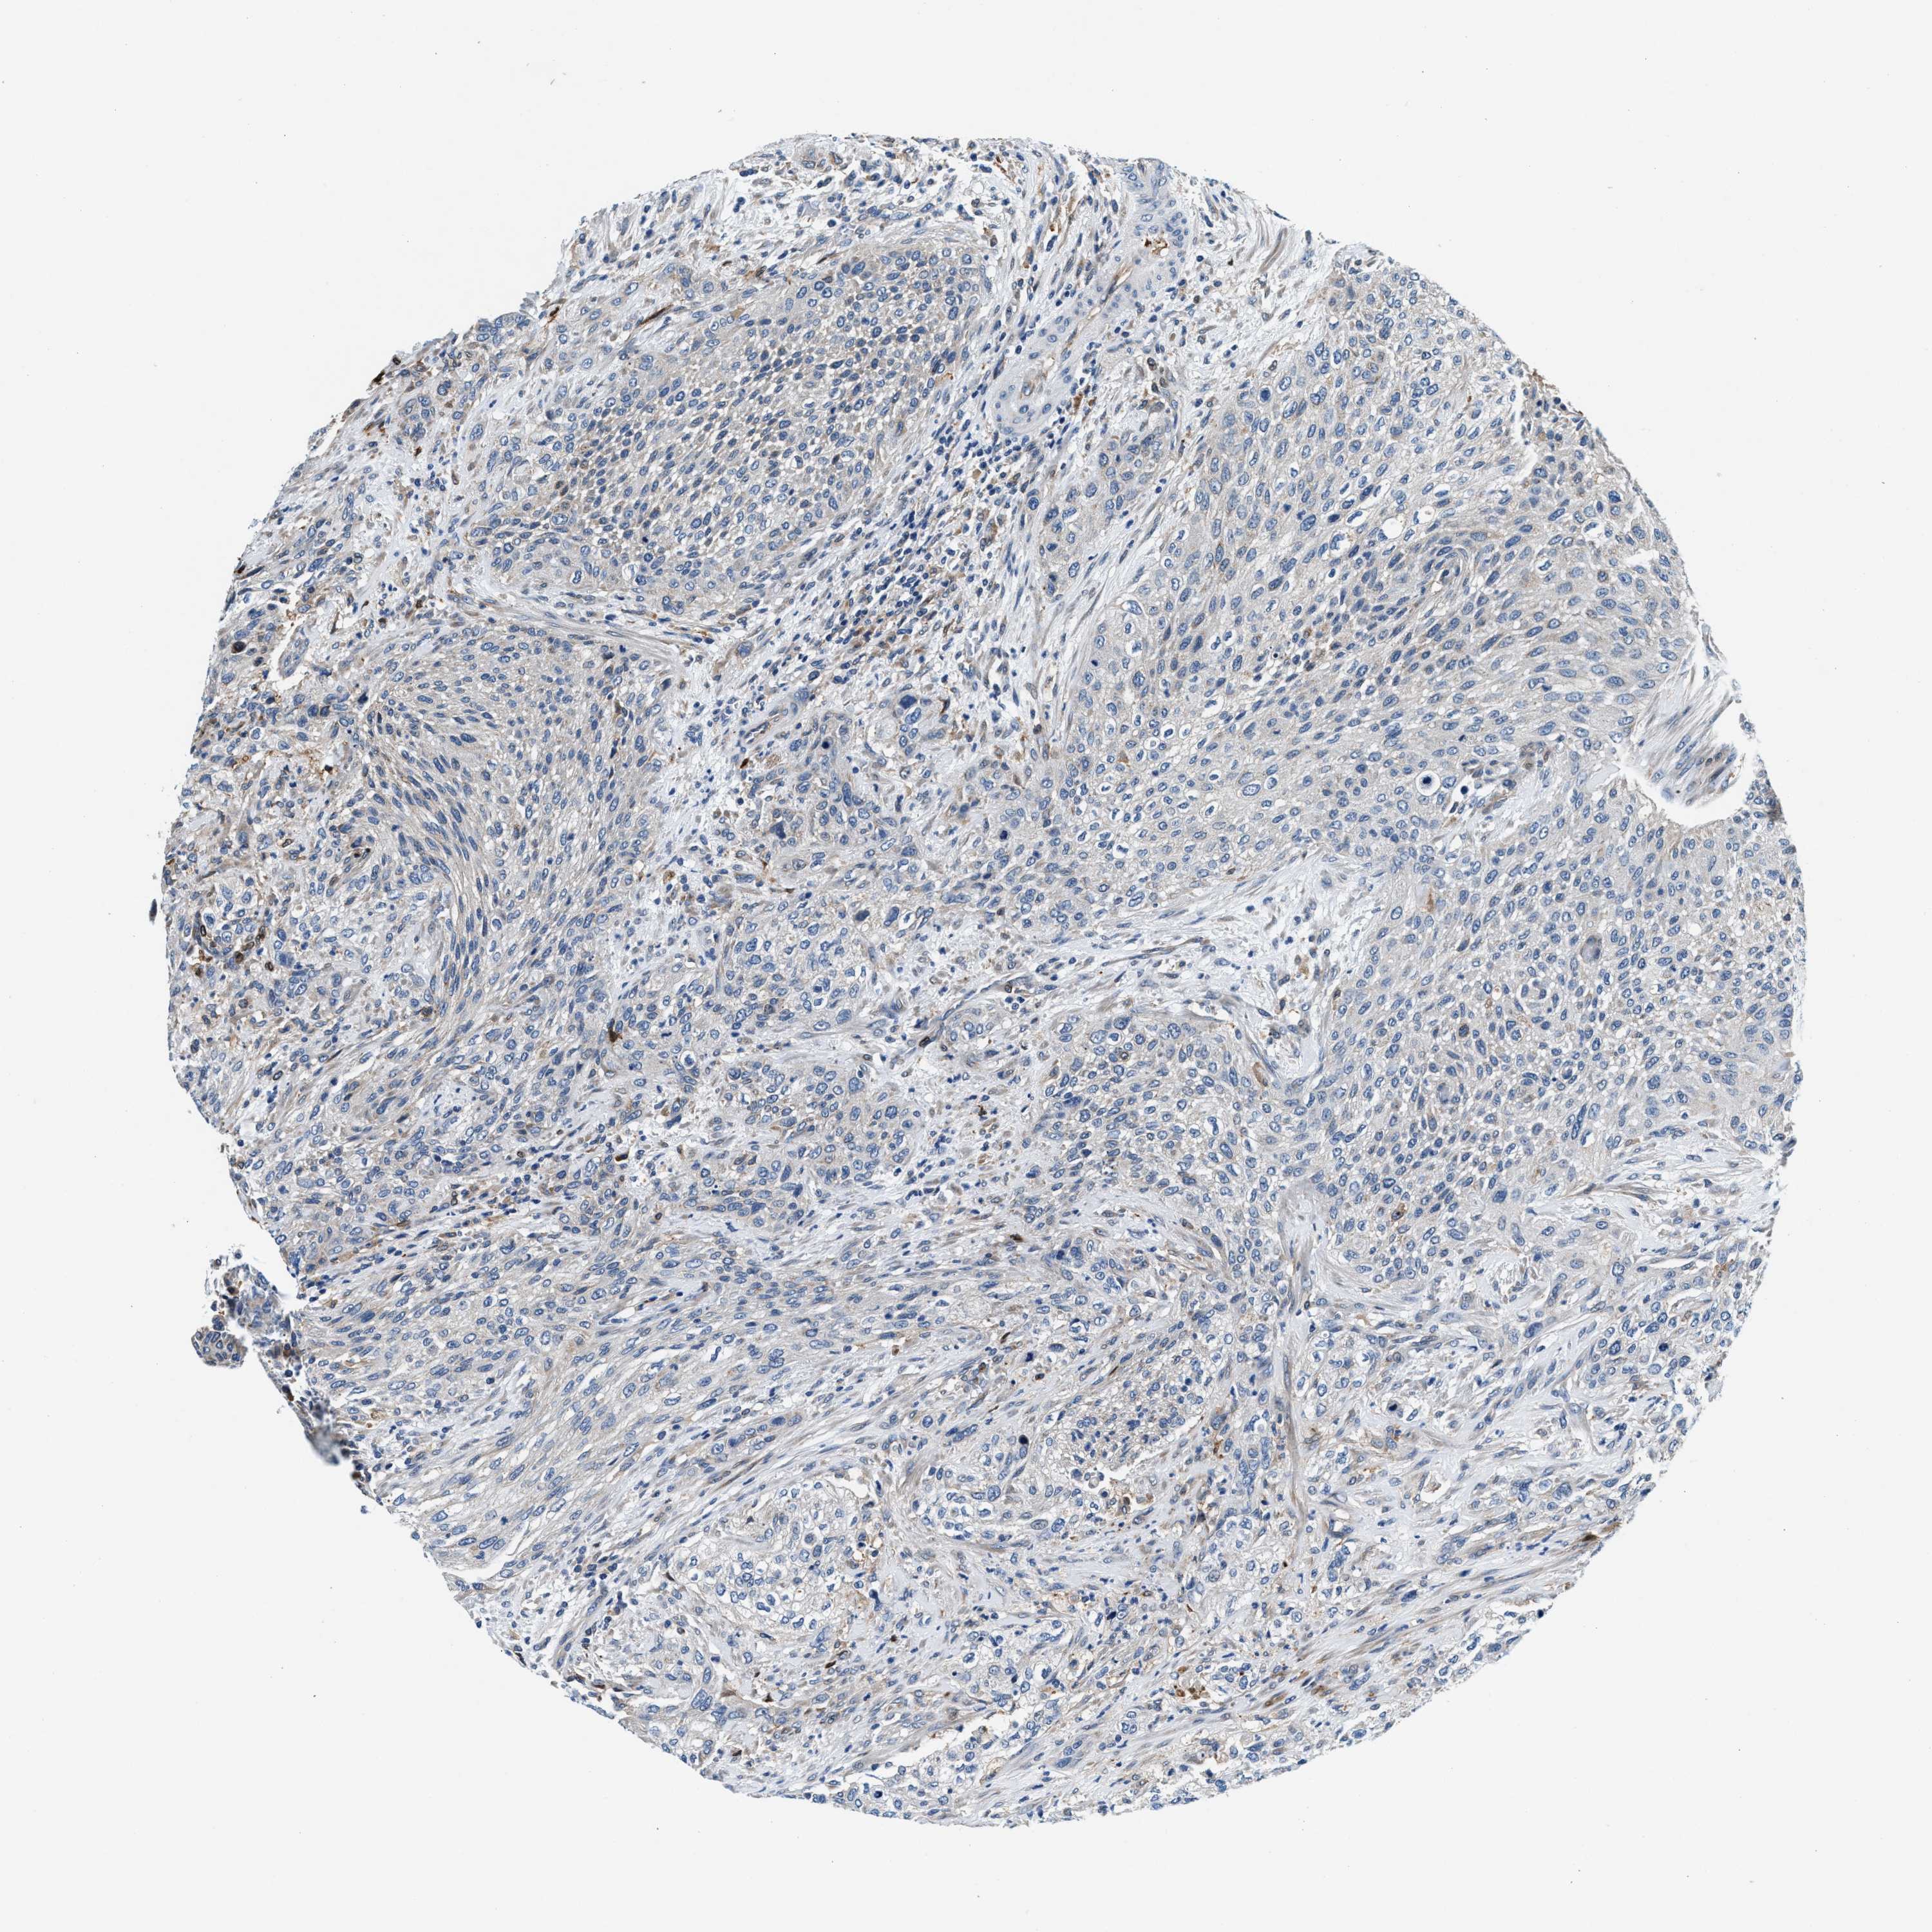

UROTHELIAL CANCER - Protein expressioni

A mouse-over function shows sample information and annotation data. Click on an image to view it in a full screen mode. Samples can be filtered based on level of antibody staining by selecting one or several of the following categories: high, medium, low and not detected. The assay and annotation is described here.

Note that samples used for immunohistochemistry by the Human Protein Atlas do not correspond to samples in the TCGA dataset.

Antibody stainingi

Antibody staining in the annotated cell types in the current human tissue is reported as not detected, low, medium, or high, based on conventional immunohistochemistry profiling in selected tissues. This score is based on the combination of the staining intensity and fraction of stained cells.

Each image is clickable and will lead to virtual microscopy that enables deeper exploration of all samples and also displays staining intensity scores, fraction scores and subcellular localization as well as patient and tissue information for each sample.

Antibody HPA023030

Staining

High

Medium

Low

Not detected

Intensity

Strong

Moderate

Weak

Negative

Quantity

>75%

75%-25%

<25%

None

Location

Nuclear

Cytoplasmic/membranous

Cytoplasmic/membranous,nuclear

Urothelial carcinoma, Low grade

Urothelial carcinoma, High grade